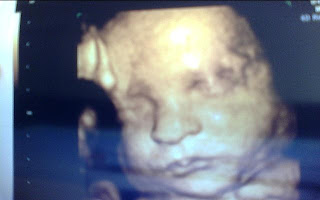

A little peek

Isn't technology amazing? This week our little guy was actually cooperating and didn't have his hand in front of his sweet little face. I was already in love with him, but now I really can't wait to meet him and kiss those sweet cheeks.

We're still waiting on the verdict from Doctor #2 about whether I stay or go home for a few weeks. I'll keep you posted. Until now here are some pictures of our little man. Sorry for the poor quality I had to use our web cam since Marvin has our camera.